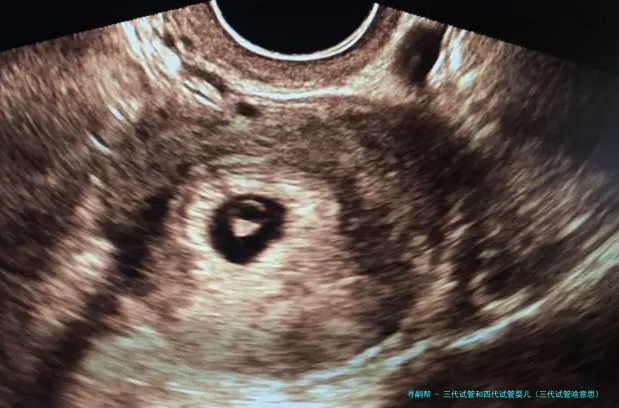

试管婴儿的医学术语称:胚胎转移技术-胚胎移植,其过程是女的一方先使用药物促排卵,再从卵巢内拿出卵子,男方拿出精子,在实验室将精子、卵子结合培育成胚胎,然后又将胚胎转至子宫腔内,令其着床、妊娠。

试管婴儿道理 “试管婴儿”其实不是真正在试管里长大的婴儿,而是从卵巢内拿出若干个卵子,在实践室里使之们与男方的精子结合,形成胚胎,然后挪动转移胚胎到子宫内,让它位于妈妈的子宫内着床、妊娠。